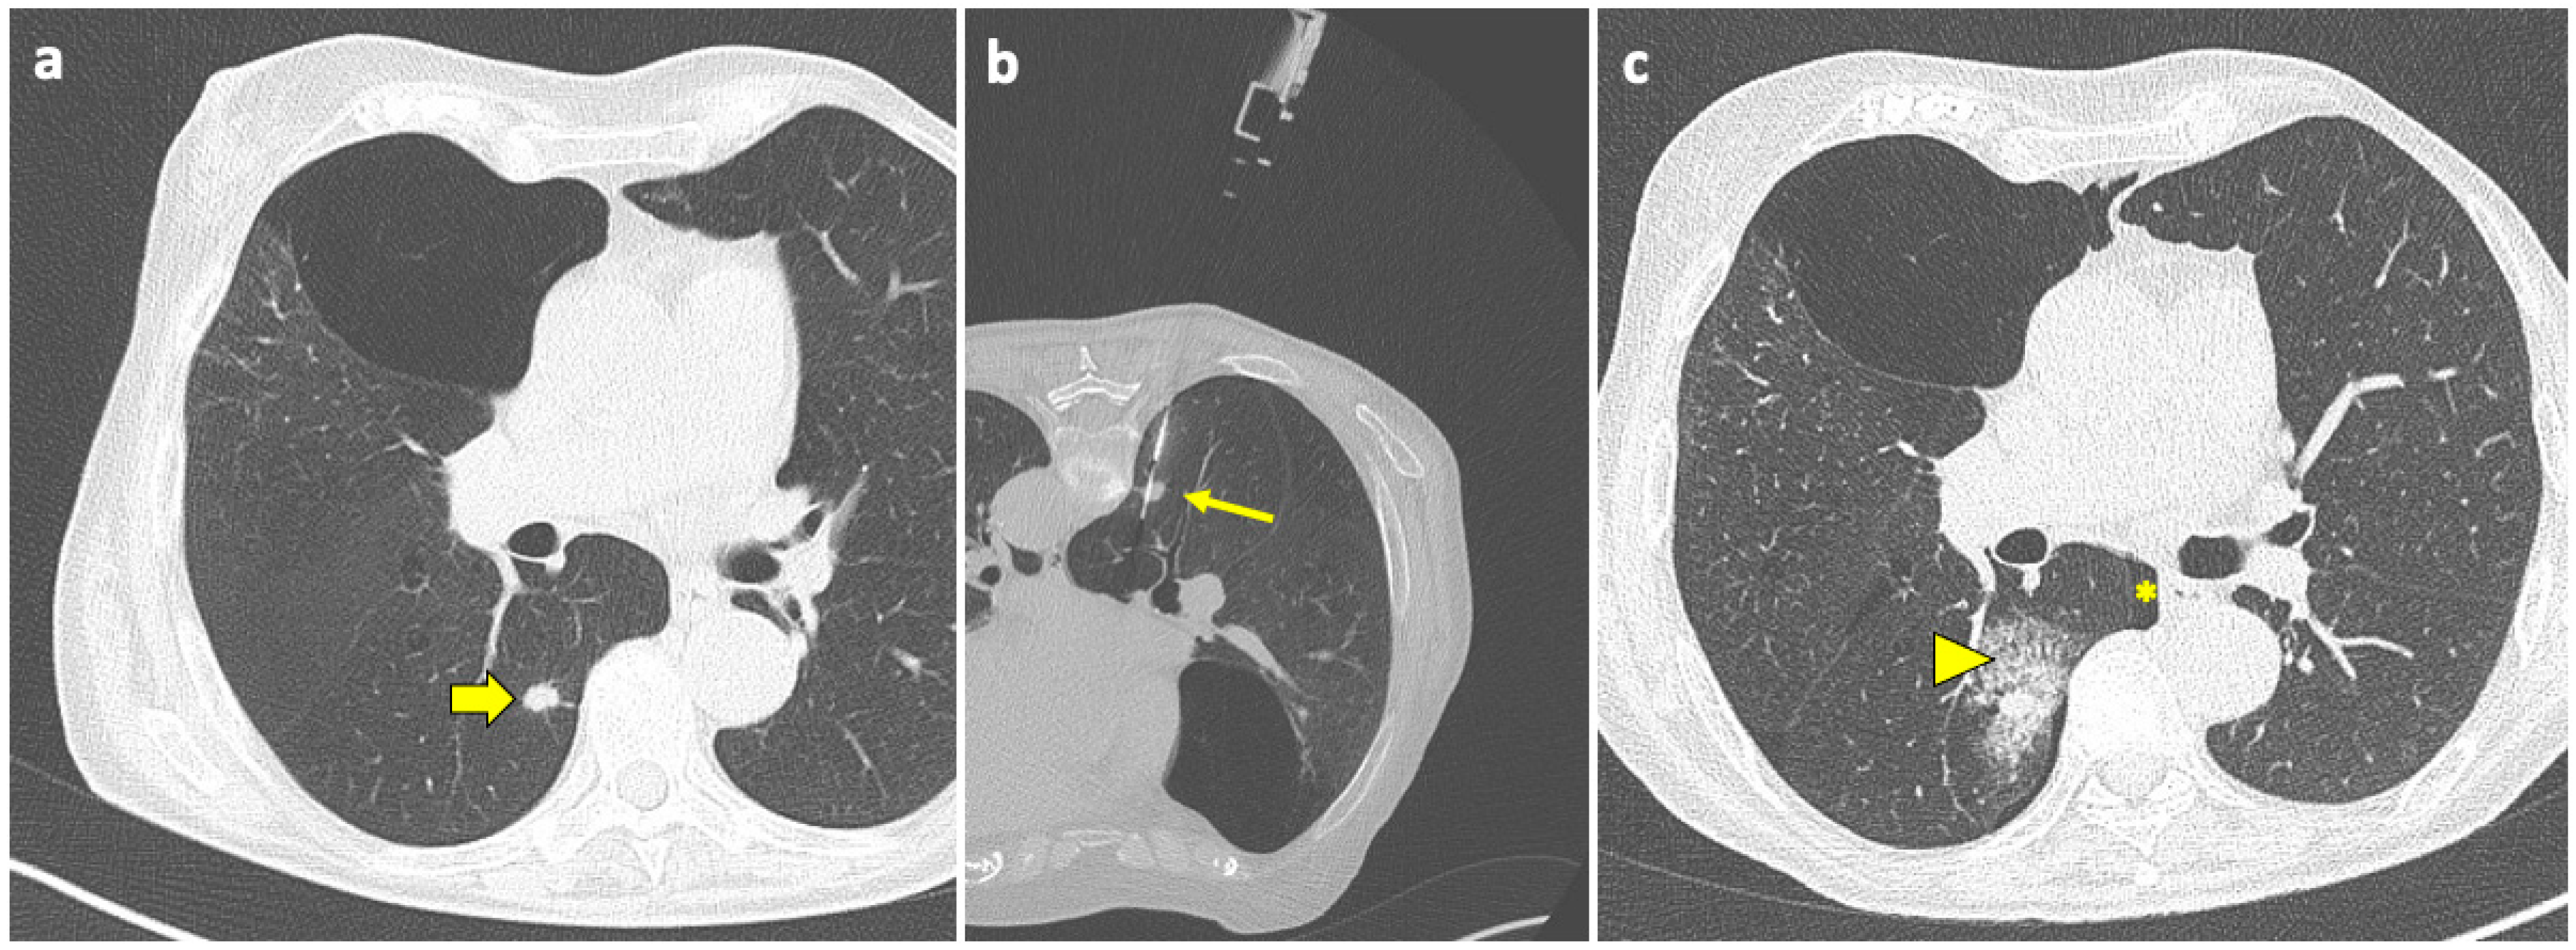

Pulmonary hemorrhage is the second most common complication after PTLB, with a prevalence ranging from 4 to 27% [94]. In the majority of cases, this complication is mild and only detected on the post-biopsy CT scans as ground-glass opacity (GGO) around the lesion or along the needle tract, representing an alveolar hemorrhage in clinically asymptomatic patients, as shown in Figure 3.

Figure 3.

Post-procedural perilesional hemorrhage. (a) New solid pulmonary nodules are discovered during follow-up of a 73-year-old woman with a history of breast and rectal cancer, including one in the right lower lobe (thick arrow). (b) With the patient in a prone position, the sample notch of a CNB system (arrow) is positioned under CT guidance at the level of the nodule, and biopsy is performed. (c) At the end of the procedure, the patient is turned into the supine position and a final CT scan is performed, which shows a minor-degree pneumothorax (asterisk), along with a ground-glass opacity and septal thickening in the tissue around the nodule, consistent with localized hemorrhage (arrowhead). Both complications had no evolution or sequelae. Abbreviations—CNB: core needle biopsy; CT: computed tomography.

Typically, no treatment is required, and the only measure that should be adopted is to position the patient with biopsy-side-down to avoid the aspiration of blood into the unaffected lung. When PH becomes symptomatic or a higher-grade PH arises, oxygen and pro-coagulative therapy may be required.